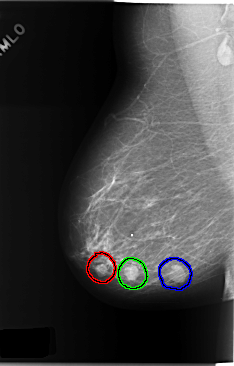

FILE: C_0174_1.RIGHT_MLO.OVERLAY

TOTAL_ABNORMALITIES 3

ABNORMALITY 1

LESION_TYPE MASS SHAPE OVAL MARGINS CIRCUMSCRIBED

ASSESSMENT 4

SUBTLETY 5

PATHOLOGY BENIGN

ABNORMALITY 2

LESION_TYPE MASS SHAPE OVAL MARGINS MICROLOBULATED

PATHOLOGY MALIGNANT

ABNORMALITY 3